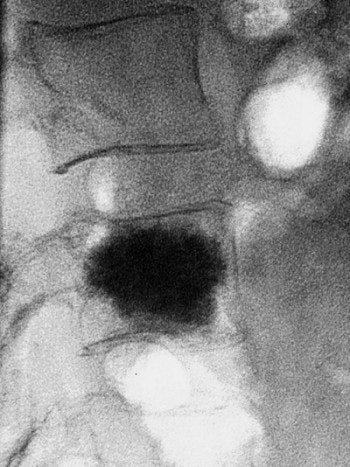

A vertebral compression fracture causing pain and spinal deformity (above). Below, a biopsy needle is guided into the fractured vertebra through a small incision in the skin. Inset shows a magnified view of the interior of the osteoporotic vertebra with the needle in place.